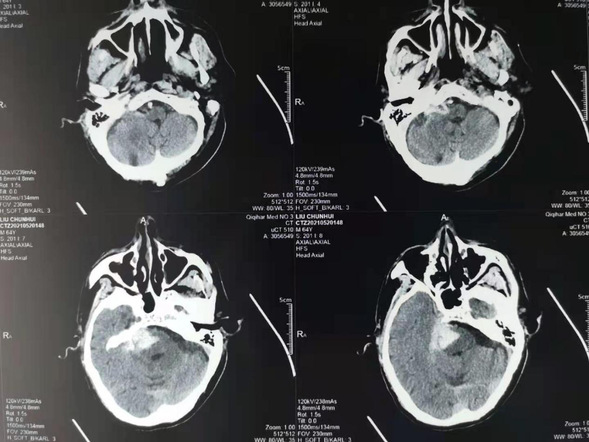

患者柳某,男性,64岁。5月20日晚突发意识障碍,送至我院,经头部CT后诊断为脑干出血。经神经外二科医疗团队讨论后决定行神经外科机器人辅助下脑干出血穿刺引流。在神经外科手术机器人的辅助下,将引流管经患者右侧小脑精准植入脑干血肿腔,手术圆满成功。

术前头CT